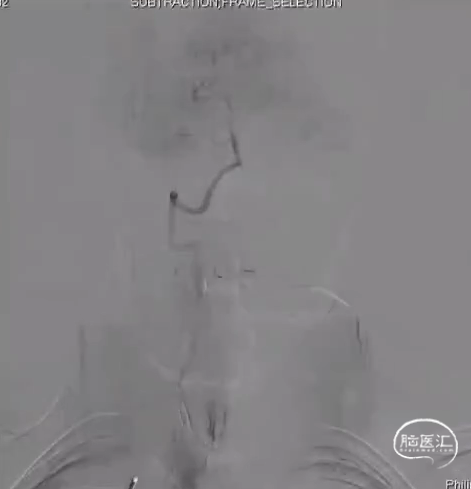

球囊由远及近扩张

Xpert支架植入

术后DSA R-CCA